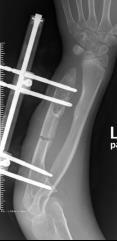

桡骨陈旧性骨折骨不连、畸形

术前 手术 术后功能恢复良好

尺骨短缩畸形并软骨瘤 桡骨小头脱位